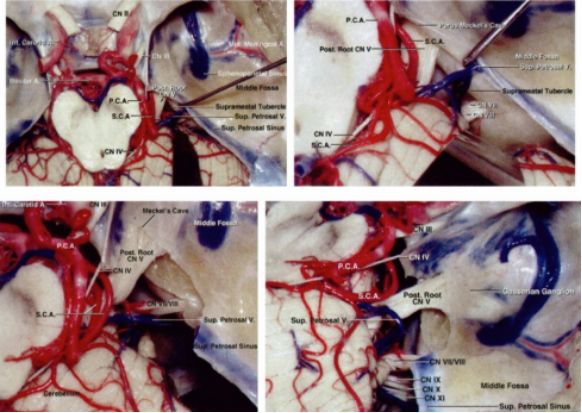

图2. 简要复习一下右侧内听道上入路的显微解剖。内听道上结节位于内听道上方,三叉神经后方。去除内听道上结节表面的硬脑膜并磨除该结节,沿着三叉神经继续显露并保持在三叉神经上方操作是安全的。即便这样做有些帮助,但是这个方法很少用于处理岩尖脑膜瘤和其它相关颅底脑膜瘤(感谢AL Rhoton,Jr供图)

图3. 岩尖和桥小脑角区上面观。三叉神经于内听道上结节内侧进入Meckel's腔,切断岩上窦并磨除内听道上结节以更好的显露三叉神经根的前部(左下图)。侧方显示通过磨除内听道上结节和打开部分Meckel's腔增加的三叉神经根显露范围(右下图)。(感谢AL Rhoton,Jr供图)